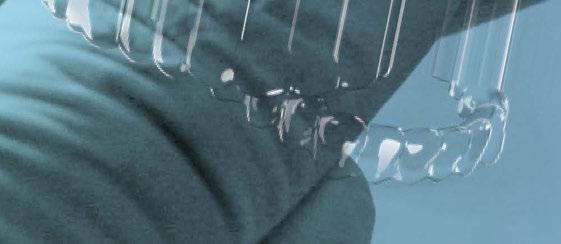

A continuación, para la planificación de los implantes dentales y el diseño de la férula de cirugía guiada se usó la plataforma digital RealGUIDE®. Para ello se realizó el matching, por un lado, del archivo STL del encerado digital; y, por otro, del archivo 3D. De esta manera, se pudo analizar el tejido óseo residual apical a cada diente y la posición de la raíz respecto a las corticales vestibular y palatina. También se estudió la relación de los contornos óseos con los tejidos blandos y con la posición final de los márgenes cervicales de la restauración protésica, pudiendo así planificar la posición 3D correcta de los implantes. En esta primera fase se diseñó una férula quirúrgica para la elevación de seno bilateral a partir del software RealGUIDE™, que nos sirvió de guía para el diseño de las ventanas de acceso. Esta férula se imprimió con la impresora 3D Formlabs® (Figura 7)

Figura 7. Férula impresa para elevación de seno con ventana lateral.

3. Fase quirúrgica final

A los 6 meses de cicatrización, se realizó un nuevo CBCT, obteniendo un nuevo archivo DICOM que alineamos con el STL del encerado. De esta manera, se planificó la posición de los implantes a 4 mm del margen de la restauración final y se diseñó y confeccionó la férula de cirugía guiada dentosoportada en 12-13 y 22-23, la cual imprimimos con la impresora 3D Formlabs®. El provisional

de carga inmediata lo diseñamos con el programa de diseño 3D Exocad® a partir del encerado y se imprimió también en clínica con la misma impresora 3D (Figuras 14-16).